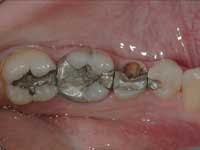

Less than one-half of the coronal tooth structure remaining (Figs. 1-6)

It is my opinion, regardless of the other factors present, that it is still advisable to place a post or posts in such teeth. Endodontically treated teeth with less than one-half of the coronal tooth structure remaining have a reduced chance of long-term service, and patients should be so advised as the treatment plan is developed.

Quality of remaining tooth structure

Assuming that there is a significant amount of coronal tooth structure remaining, the quality of the remaining tooth structure should be considered. Often, remaining tooth structure has discolored areas, slightly demineralized areas, cracks, undermined areas, or other negative characteristics. Removal of tooth structure with these characteristics allows a realistic and necessary appraisal of the amount of viable tooth structure remaining. After removing the affected areas, the same suggestions stated in the previous section on quantity of tooth structure remaining apply. Posts are often indicated.